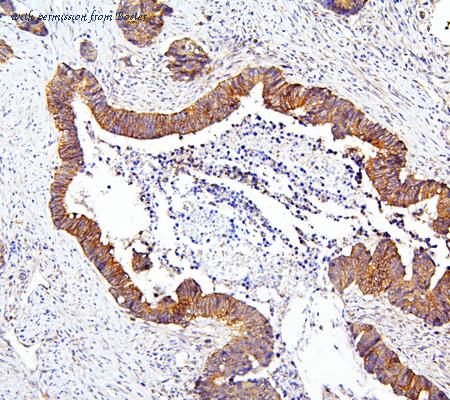

gene information - man mTOR

- synonym:FRAP; FRAP1; FRAP2; RAFT1; RAPT1; SKS

- description:mechanistic target of rapamycin kinase